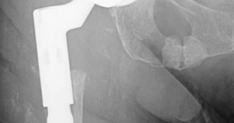

History of presenting complaint : Presents with a draining wound and well-fixed cementless components with a constrained liner due to absent abductor mechanism (Fig. 19.12). Treated with Prostalac and six weeks of IV antibiotics (Fig. 19.13). At the 6-week point, the patient sustained a ground level fall with an acetabular fracture and displacement of the acetabular Prostalac (Fig. 19.14).

(Figs. 19.12, 19.13, and 19.14)